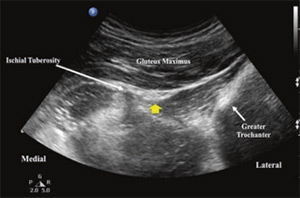

محل عصب سیاتیک در تصویر سونوگرافی زیر با فلش زرد نشان داده شده است: